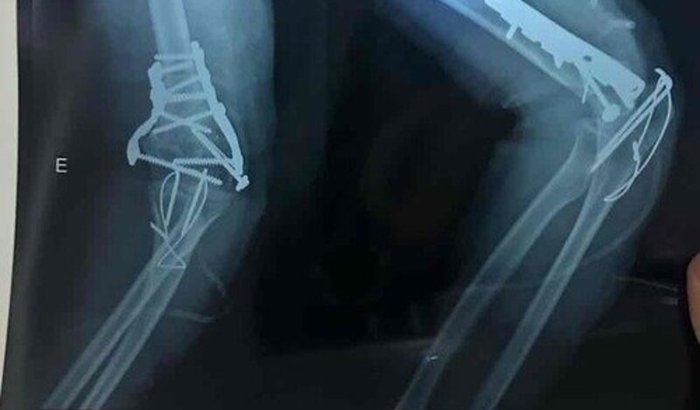

Sofri um acidente (queda) no dia 01/03 e acabei fraturando o úmero distal inferior do cotovelo, aguardei por dias na fila da regulação e consegui fazer a cirurgia no dia 13/03 pelo SUS, porém, pra fazer a fisioterapia não consegui vaga. Todo o dinheiro arrecadado nessa vakinha será pra custear meu tratamento que durará em torno de 6 meses segundo o médico, que é a única forma de eu conseguir retomar minhas atividades pois meu braço perdeu grande parte da mobilidade, conto com a ajuda de vocês 🫶🏻